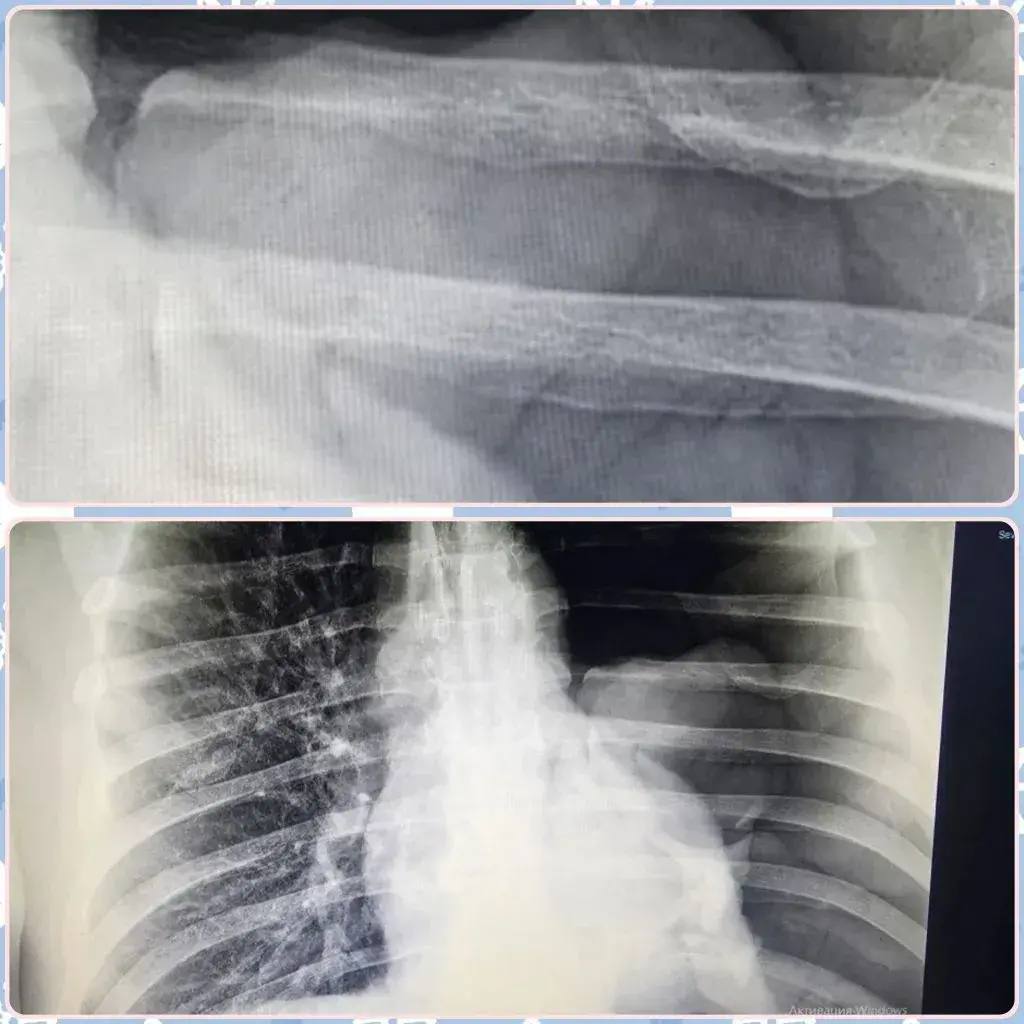

Один из пострадавших - 49-летний житель села Маянга. Мужчина упал с двухметровой высоты, но не стал сразу обращаться к врачам. Лишь через три дня, когда усилилась боль и появилась одышка, он приехал в больницу. Диагноз - левое легкое полностью "сдулось" из-за скопления воздуха в грудной полости. Хирурги экстренно установили дренаж, чтобы восстановить дыхание. Пациента удалось спасти.

Еще один пострадавший - 57-летний мужчина из села Еланка. Мужчина сорвался с трехметровой высоты при монтаже оборудования. Его привезли в больницу в состоянии шока и с нарушением дыхания. Сейчас за его жизнь борется команда врачей. Уже проведена операция по дренированию легкого.